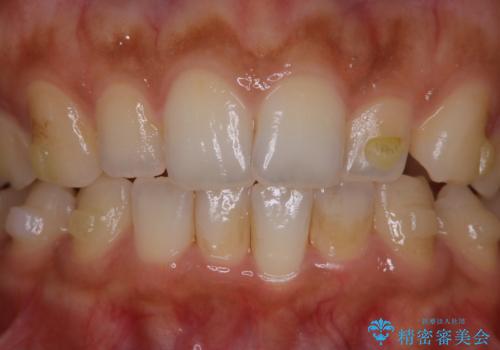

- インビザラインでの矯正治療中に、着色や汚れが気になるとのことでした。PMTC60分コースを行いました。

インビザライン治療中には、歯の表面にアタッチメント(効率的に歯の移動をするもの)を設定します。そのため歯ブラシでは届きにくい細かい部分などに、歯石や着色がついてしまうことがあります。着色などを放置していると、着色なのか、虫歯なのかの判別もしずらく正確にお口の中の状態を診断できません。